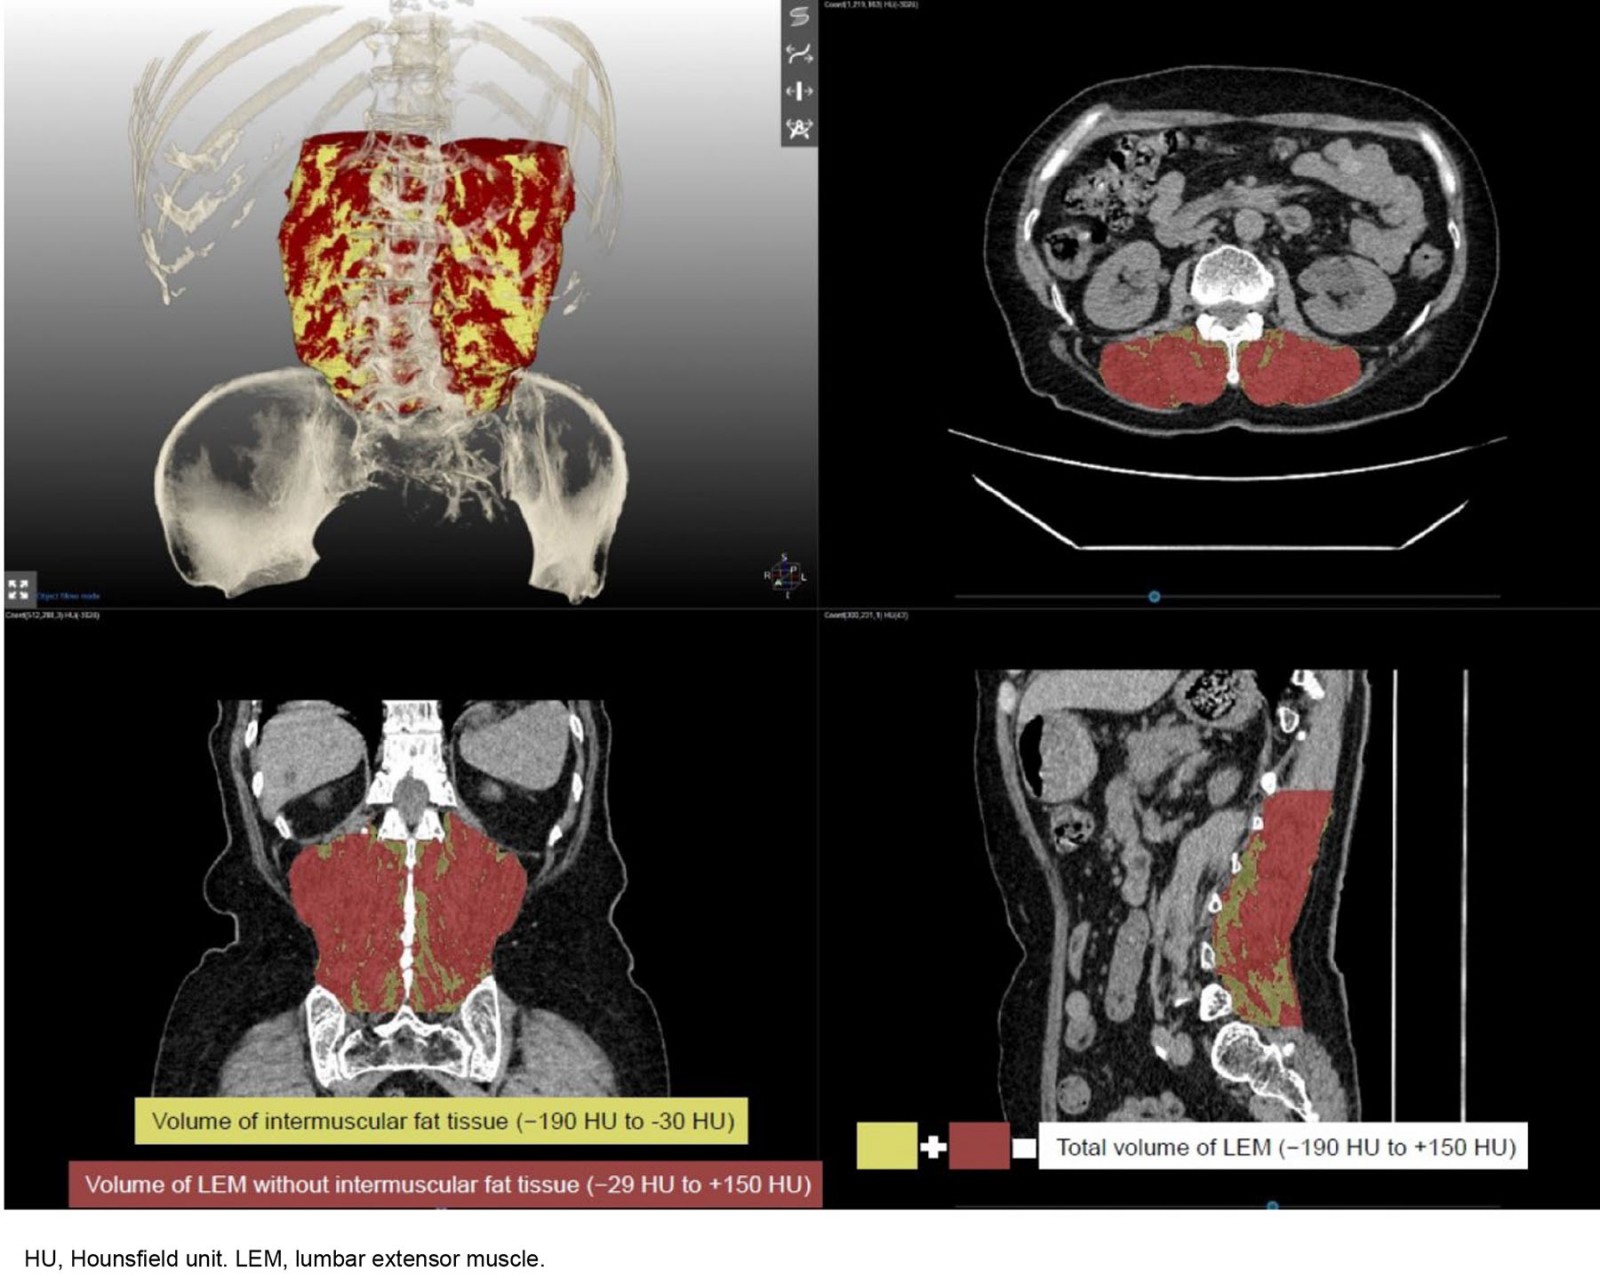

All participants were examined by CT scan (Revolution EVO; https://www.gehealthcare.ca/en-ca/products/computed-tomography/revolution-evo-gen-3). Before each CT scan, calibration was performed using air as the standard. CT scanning was performed with each patient in the supine position with a routine lumbar CT scan protocol at 120 kV and 140 mA. Using 0.625 mm thin-section axial CT scan images, three-dimensional (3D) volume rendering and multiplanar images were reformatted using a radiological workstation (MEDIP; https://medicalip.com) specially designed for such purposes. We used a semiautomatic 3D segmentation algorithm, the graph-cut technique29, for volumetric muscle segmentation with MEDIP. During the segmentation procedure, the musculoskeletal radiologist with more than 15 years of experience repeatedly modified and confirmed the segmentation results using MEDIP.

The volume and mean density (in Hounsfield units (HU)) of the lumbar extensor muscle (LEM; multifidus and erector spinae) were calculated from the 3D segmentation of the LEM muscle. The total volume of the LEM, including intramuscular fat tissue, was measured by segmentation from the upper endplate of the first lumbar vertebra to the lower endplate of the fifth lumbar vertebra. The mean density of the LEM was also calculated as the average HU value of the pixels within the LEM volume and reflected the degree of intramuscular fat content because the HU values decreased as the fat content increased. Additionally, predefined HU ranges (–29 to +150 HU) were used to measure the volume of the LEM without intermuscular fat tissue (Fig1).

Figure 1: Three-dimensional segmentation of lumbar extensor muscle. The total volume of lumbar extensor muscle with intramuscular fat tissue displays between −190 and +150 HU, and predefined HU ranges were used to demarcate intramuscular fat tissue (yellow volume, −190 to −30 HU), and muscle tissue (brown volume, −29 to 150 HU).